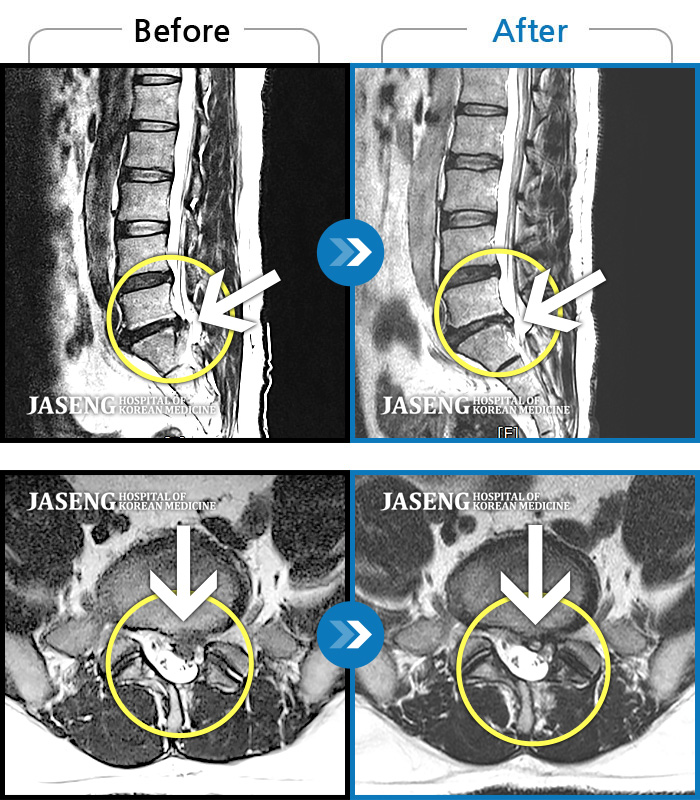

40대 초반 여성 환자인데요,, 처음 선생님 뵈었을 때에 1번,4,5번허리디스크 증상도 증상이지만,

본인 나이에 비해서 10~15년정도 퇴행이 많이 되어있어서 전체적으로 관리가 많이 필요하다고 설명해주셨구요,,

그당시 원장님진료실에서 보았던 저의 엠알아이사진이 아직도 생생히 기억이 납니다 ^^

뼈부분의 색이 왜저렇게 검냐고 여쭈어 보았더니, 말씀주신데로 "퇴행이"많이 되어서 그렇다고 설명해주시면서,,

그렇다고 당장 크게 머가 안좋거나 그런건 아니고,, 퇴행된 뼈자체를 새것으로 되돌릴수는 없지만,,

꾸준히 치료받으면서 관리만 잘한다면 건강한 뼈를 가진 사람과 동일하게 건강한 생활 충분히 가능할수 있다고,, 긍정적으로 말씀을 주셨어요...